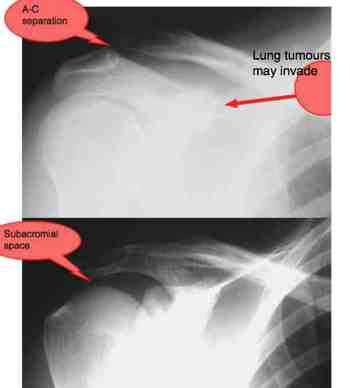

Notice the space between the ball of the humerus and the overhanging acromion. It's through this space that the tendon of the very important supraspinatus muscle passes.

Very occasionally tumours of the lung may invade the shoulder. Smoker? Expect trouble, because it's coming.

Within the subacromial space lies a bursa, protecting the supraspinatus tendon from a friction rub against degenerative changes in the overlying AC joint. The bursa is richly endowed with nerve endings and mechanoreceptors from the C5/6 nerve roots; hence the strong association between neck and shoulder pain. Spurling's test is used to decide if it is a frankly pinched nerve or a shoulder condition.